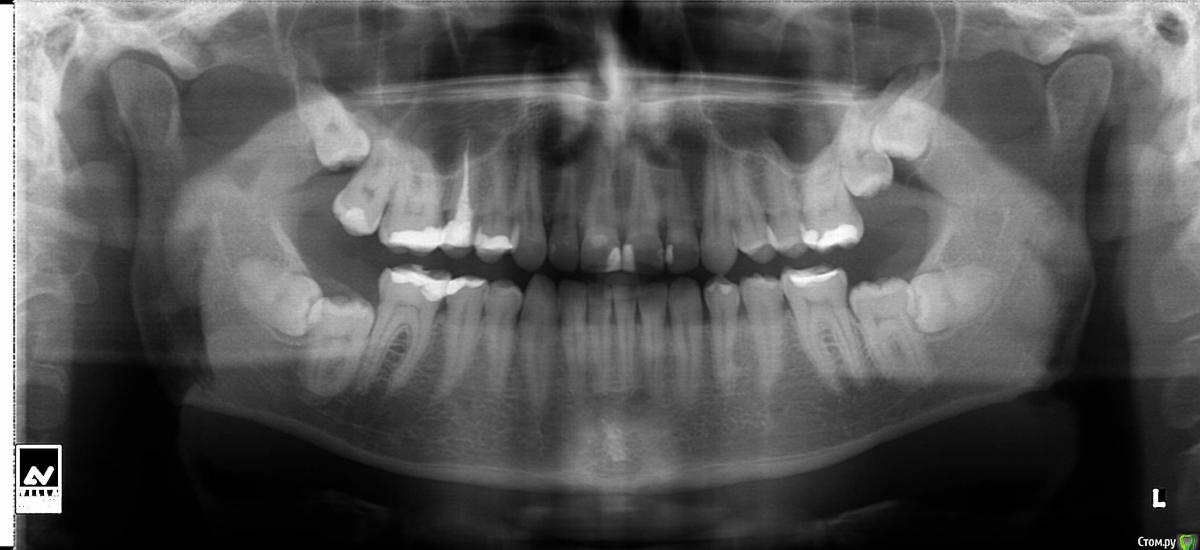

Mel18 Опубликовано 13 января, 2015 Поделиться Опубликовано 13 января, 2015 Доброго времени суток и с наступившими праздниками! Живя всю жизнь без 7 и 8 не знал беды, пока один из форумных докторов (спасибо ему) не сказал, что пора бы дёргать крайние зубки. Походил по местным хирургам: один с удовольствием расписал все ужасы выдергивания, 2 других сказали, пока ничего не трогать, якобы раз столько времени с ними ходил и всё ок до сих пор, то и поводов особо нет...Кому верить? Вопрос знатокам! Что же всё-таки с ними делать? Чем это чревато (прикус, кариес?)? И сколько у меня на это есть времени, и на сколько быстро беда может прогрессировать? Ссылка на комментарий

kladoffka Опубликовано 14 января, 2015 Поделиться Опубликовано 14 января, 2015 Думаю, что все же стоит удалить, в данном случае позиция "не беспокоит - лучше не трогать" не совсем верна, т.к. потихонечку 8ки начнут разрушать 7ки. Если удалить 8ки, которые блокируют 7ки , то вполне вероятно, что эти семерки со временем и вылезут нормально.По поводу удаления - я бы сделал 3д снимок и ориентировался по нему - проще удалить и прогнозировать.Все вышесказанное ИМХО, интересно что скажут старшие коллеги. Ссылка на комментарий

faity Опубликовано 30 июня, 2015 Поделиться Опубликовано 30 июня, 2015 спасибо и пожалуйста) по поводу КТ: смещение носовой перегородки, ассиметрия костей лицевого черепа, восьмерки удалять, брекеты ставить и это блин самый убогий КТвьювер из тех что я видел, плюс снимок не полный, не видно углов челюстей в которых лежат нижние восьмые и суставов височно-нижнечелюстных. Ссылка на комментарий